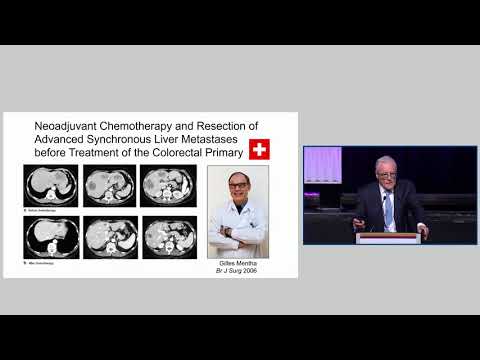

DEB07: Synchronous Liver Metastases and Rectal Carcinoma Sequential vs Simultaneous

Debate 07: Synchronous Liver Metastases and Rectal Carcinoma Sequential vs Simultaneous